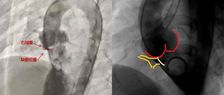

近期,沈阳医学院附属第二医院马晶茹教授团队成功应用MemoLefort左心耳封堵器,为一名71岁高龄房颤患者完成完成“射频消融+左心耳封堵”一站式手术。由于该病例心耳位置较低,术者选择房间隔低位穿刺,满足更好轴向,避免心耳上缘压迫,后通过DSA与ICE精准指引,利用MemoLefort封堵器的贴壁成角倒刺设计实现稳固锚定与严密封堵。